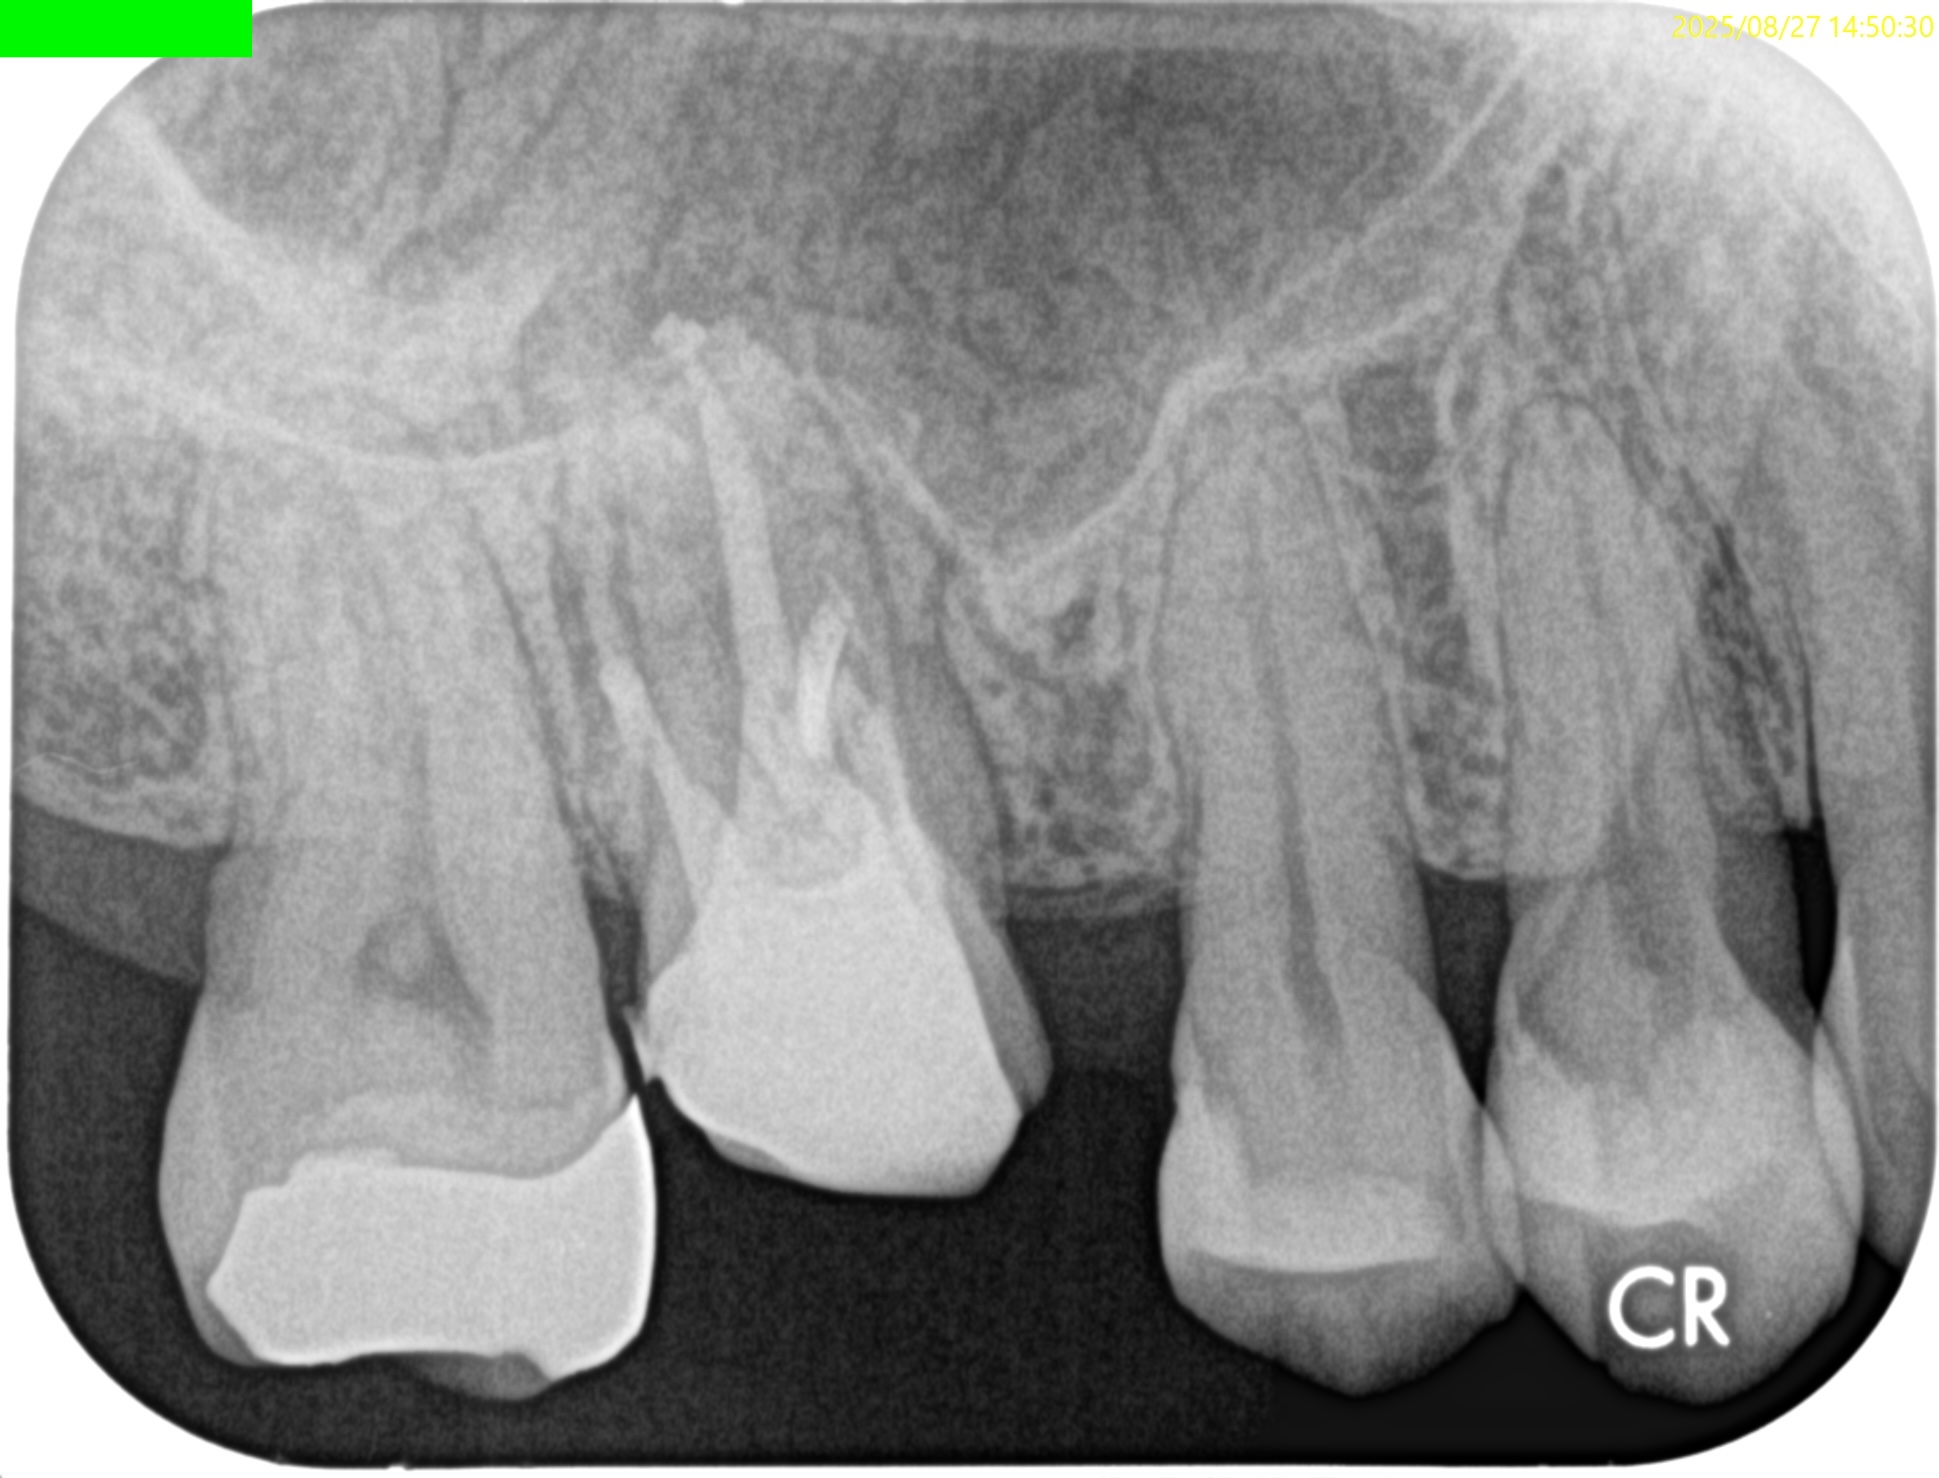

術後にPA, CBCTを撮影した。

MB

DB

B

問題はないだろう。

#3 MB, DB Apicoectomy 7M recall(2026.3.30)

P

7ヶ月前と比較した。

劇的に歯槽骨の開創は回復している。

そしてP根だが、根尖病変の治癒とともに口蓋側の骨欠損が大きく回復しているのがわかる。